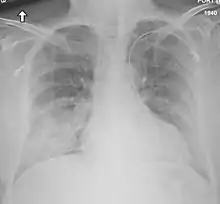

Chest X-ray of a case of MERS

Chest X-ray findings tend to show bilateral patchy infiltrates consistent with viral pneumonitis and acute respiratory distress syndrome (ARDS). Lower lobes tend to be more involved. CT scans show interstitial infiltrates.[29]